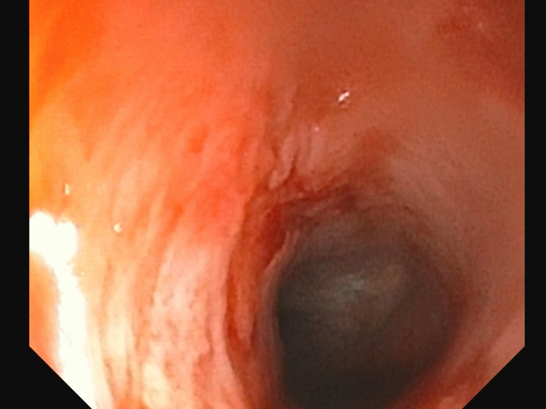

拡張後の鼻咽頭部

約3ヶ月前より鼻炎症状を主訴に他院を受診し、鼻炎としての治療が行われたものの、十分な改善が見られなかったため、精査を目的として当院を受診されました。 当院にてCT検査を実施したところ、鼻咽頭部に顕著な狭窄を認めたことから、呼吸器症状の改善を目的に、鼻咽頭狭窄に対するバルーン拡張術を実施しました。 処置後の経過は良好で、全身状態も安定していたため当日退院としました。 その後も経過観察を継続しており、現在までに7ヶ月が経過しましたが、再発は認められていません。